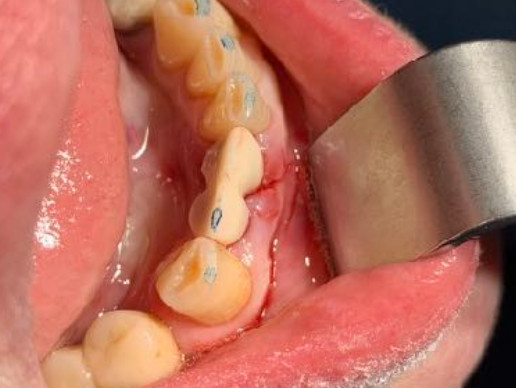

Età

66 anni

N.impianti esistenti

4

N.impianti inseriti

1

Zona dentale

41

Densità secondo Misch

D2

Carico occlusale

Immediato in leggera occlusione